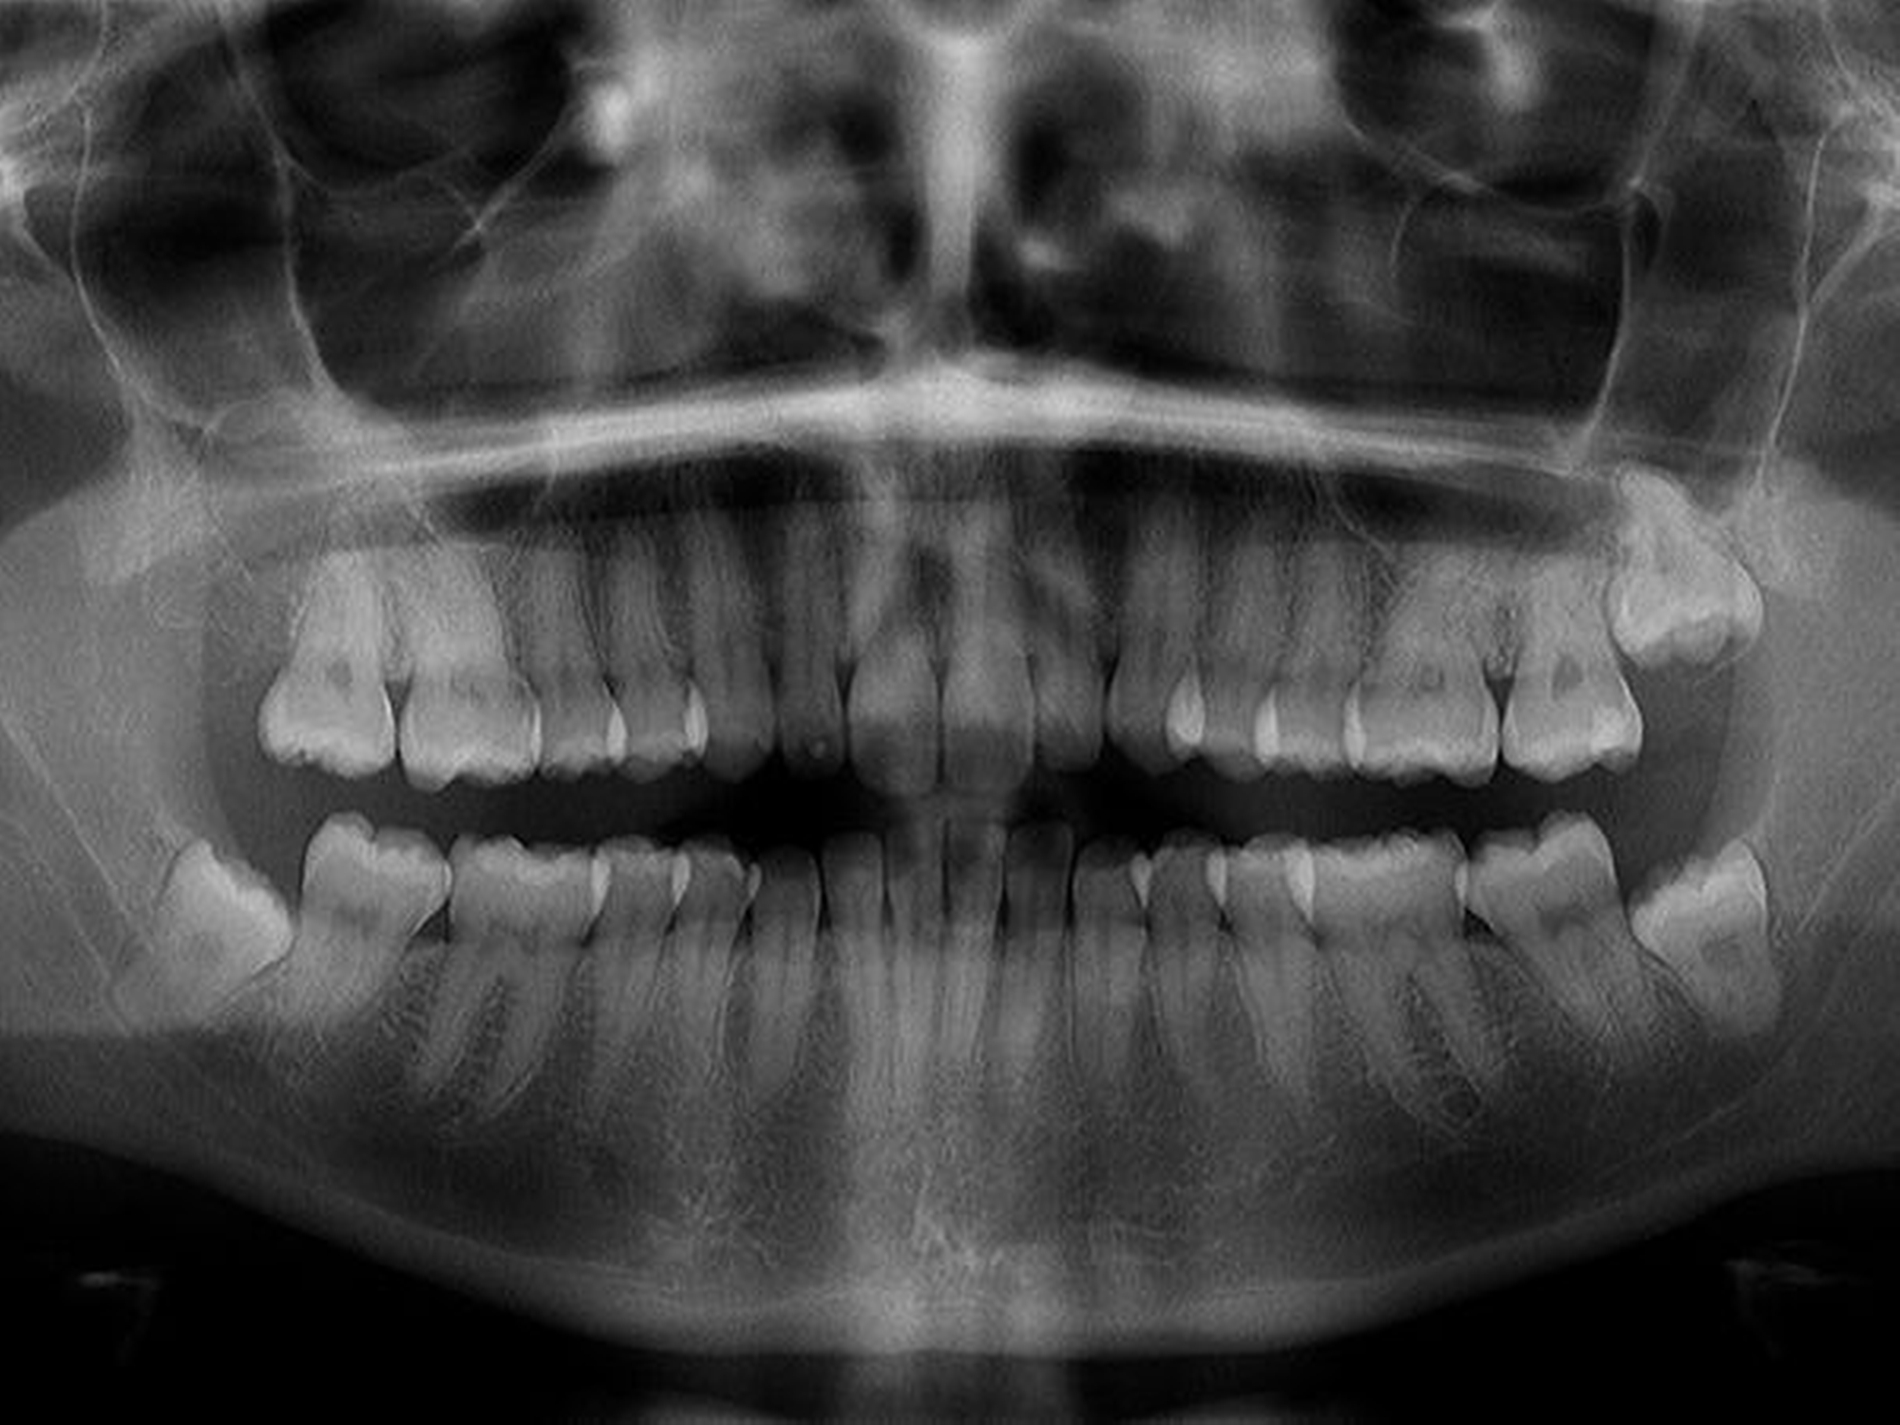

Nach erfolgtem Eingriff unter stationären Bedingungen konnte die Nachbehandlung ambulant in unserer Praxis erfolgen und gestaltete sich im wesentlichen störungfrei. Die Röntgenkontrolle nach vier Jahren zeigte operationsbezogen einen Normalbefund (Abbildung 4): Kieferhöhlen rechts und links (soweit beurteilbar) lufthell, Zähne 28, 38, 48 in etwa orthograd (also: Verlaufsbeobachtung vertretbar).

Die anderen Zähne im I. Quadranten blieben vital, die infraorbitale Sensibilität hatte sich innerhalb kurzer Zeit (Wochen) normalisiert, die Doppelbilder waren verschwunden. Die Patientin äußerte sich im weiteren Verlauf sehr zufrieden über Diagnostik und Therapie. Sie hatte auch keine Beschwerden mehr verspürt. Die Zähne 28, 38, 48 wollte die Patientin bis heute nicht entfernen lassen.